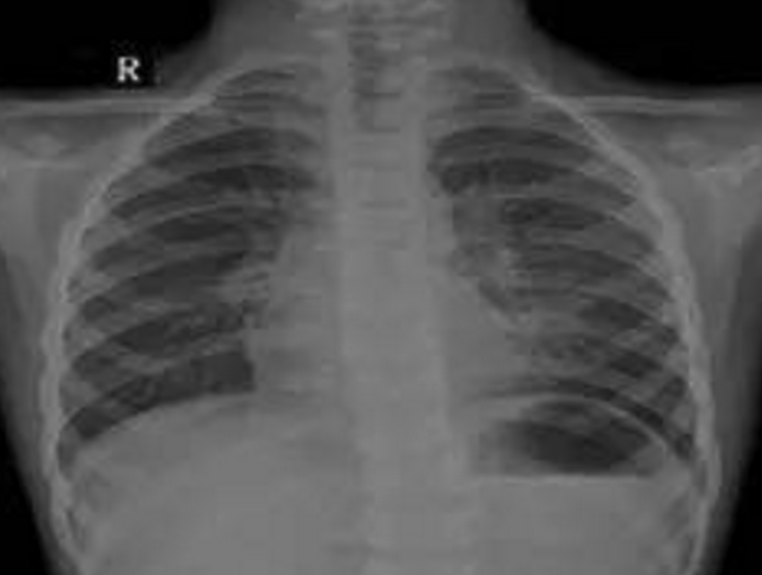

小文渊、小文博兄弟

2016年9月30日,39岁的徐士霞生下一对孪生宝宝孩子。然而孪生宝宝的降生只给这个家庭带来了三天短暂的欢乐。10月2日,小文渊、小文博相继出现抽搐、口吐白沫现象,齐齐哈尔第一医院诊断为先天性心脏病,并发肺炎、肺衰竭、呼吸衰竭,双双住进重症监护室。

5月11日下午,夫妻俩抱着文渊抵达上海儿童医学中心,经过检查,文渊重症肺炎、重度支气管炎,再不及时手术,会导致呼吸衰竭、心力衰竭。听着医生的诊断结果,夫妻俩泣不成声,家里的文博情况比哥哥还要严重,治疗费就像两座大山一样压在了夫妻俩肩上。

据有关统计,先天性心脏病已经取代原来的唇腭裂、多指,成为了新生儿出生缺陷的病种,而且还在呈现上升趋势,并成为导致5岁以下儿童死亡的首要原因。发病人数近10年增加了2.56倍,我国每年都将新增15万~20万先天性心脏病患儿,已经连续几年成为新生儿、婴幼儿时期死亡的主要原因。

有关数据显示,35岁以上的高龄产下先天性心脏病婴儿的几率为25%。这主要是由于高龄产妇在怀孕时已经超过了较佳生育年龄,卵子在分裂的时候易发生染色体异常,导致胎儿患先天性心脏病的几率增大。除此以外,遗传因素,环境因素如孕期受到辐射、药物影响、孕妇处于高原环境等也是产生胎儿先天性心脏病的重要原因。